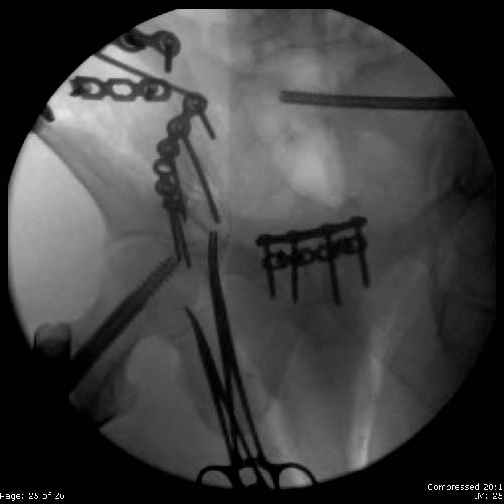

Here are the postop fluoros.

Fluoroed L SI joint and it seemed stable, but wide. So, applied c-clamp to try to squeeze down L SI joint (and note, on the last slide attached, that it's still wide), and got it closer. Single perc Iliosacral screw 40mm thread.

PS - as for the femur -- I had an idea about the malreduction in flexion, varus & ext rotation after seeing my colleague's postop fluoros from the nailing. I first recognized the actual magnitude of the malrotation after transferring the pt to the OR table for ORIF of his pelvis, and did not have consent for revision, among other

issues. I've since spoken with the first surgeon (who did the femur nailing) and we will address that, probably together, ASAP, but before the pt leaves the hospital.